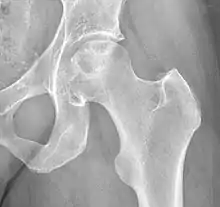

![]() | |

X-ray of hip with femoral head osteonecrosis | |

ANFH can only be diagnosed by MRI of the hip and X-rays of the hip specifically in the anteroposterior and frog-leg lateral poses.[2] Along with these scans an additional bone scan needs to be done which allows doctors to see the activities of bone cells in a body. Once the images that the physician want are obtained, they are then measured through two systematic reviews.